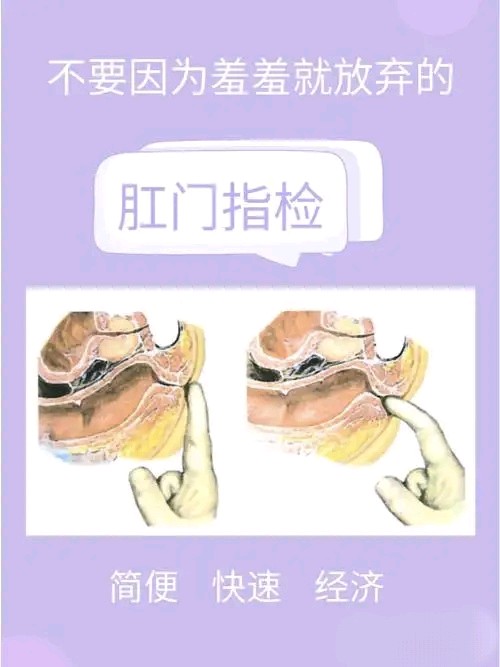

慢性便秘患者诊断过程中的一项基本且重要的体格检查。用于筛查慢性便秘的潜在原因、分型以及决定进一步检查和治疗策略。

方法:医生用手指触诊直肠。

作用:属于基础检查,评估

1.直肠腔内容物:直肠内部结构、直肠脱垂、直肠肿瘤、粪便嵌塞、直肠肿块、直肠狭窄。

2.肛门直肠功能:包括肛门括约肌张力、直肠收缩能力。如果括约肌功能异常,需进一步行肛门直肠压力测定明确诊断。

3.盆底功能:排除盆底肌功能障碍、肛门失弛缓症(Anismus)等。

4.器质性病变:直肠内是否有异常(如肿瘤、狭窄)。

5.排便时的肌肉协调:通过模拟排便动作,评估直肠和肛门括约肌的协调性。 排便时直肠未能正常扩张,肛门括约肌未能放松,提示肛门失弛缓症或盆底失调综合征。如果功能异常,需进一步行肛门直肠压力测定和盆底肌电图检查。